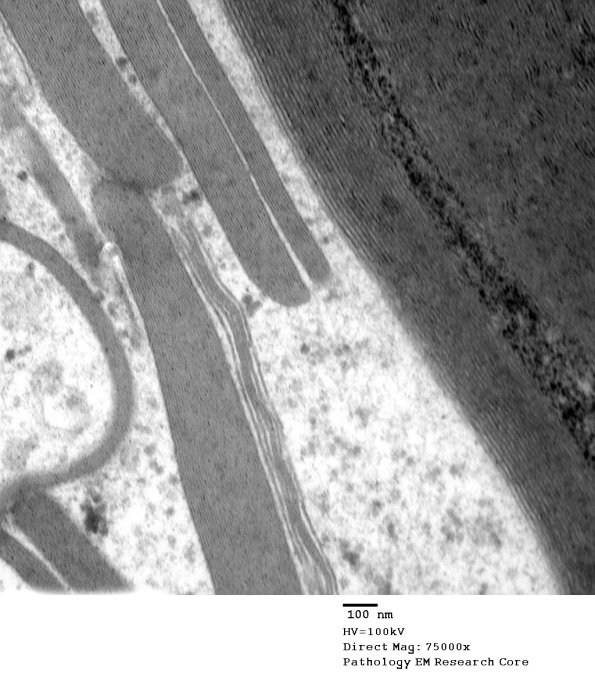

Higher magnification of image #12A1. (electron micrograph)